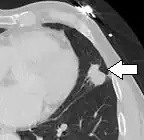

Lung nodule abutting a pulmonary cyst.[9]

• A lung nodule abutting a pulmonary cyst is a rare finding, yet indicating cancer.[9]